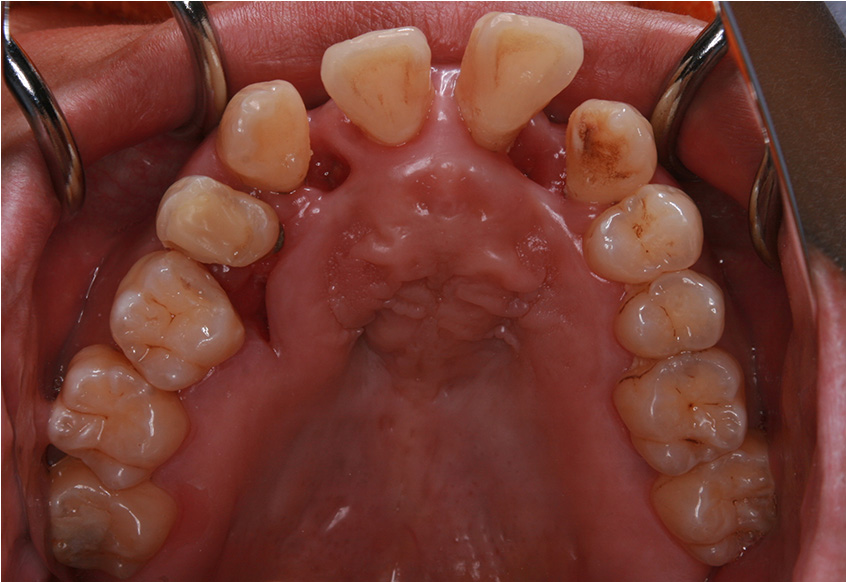

治療開始後3ヵ月経過すると、前歯の隙間や全体の乱れが減ってきました。口笛が吹けるようになったとのことです。

最初のお口の中 治療開始3ヵ月後

6ヵ月経過すると、矯正治療を終了し、前歯に被せ物の治療を行いました。

最初のお口の中 2025/3/22

被せ物装着

| 治療内容 | 上顎側切歯を2本抜歯した後、上顎の歯にブラケットを装着し、ワイヤー、矯正用ゴムで歯の移動を行いました。その後、被せ物の治療を行って治療を終了しています。 |